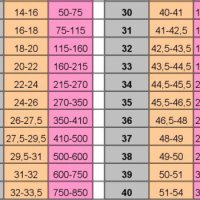

коли лікарі кажуть про передчасні пологи то обумовлюються що краще семимісячний дитина ніж восьми. сенс тут простий Плід вже має масу 1800-2100 г, зріст 40-41 см. До кінця цього терміну його легені почнуть у всю продукувати сурфактант і будуть здатні дихати без спеціальної апаратури. Плід повністю розвинений, його шанси вижити у випадку передчасних пологів значно підвищилося. Однак підшкірної жирової клітковини ще надзвичайно мало, тому його шкіра тоненька і має червоний колір. такий новонароджений дуже погано утримує тепло і при народженні потребує інкубаторі або грілці. тільце його все поки покрито пушком і сировидним мастилом, вушні раковини ще дуже малі, але вже починають розправлятися, у хлопчика яєчка опускаються в мошонку. Але ... але ... якщо раніше у нього легкі струму починали що то там робити те тут вони на половині шляху. уявіть себе в ситуації коли ви струму почали розсипати а вас різко колотнулі)) перша реакція шок так відбувається і з легкими дитинку. тому на півдорозі вони іноді відмовляються працювати.